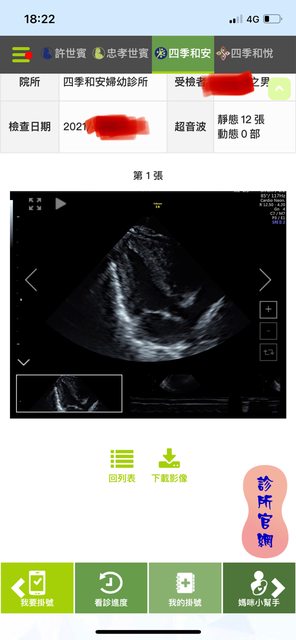

我有印象這篇文 那你要說文字很像我也沒話說 還是我拿三胎的超音波照給你? 第一胎在台北生的 二三胎後來都在禾馨看 https://i.imgur.com/Ohujwd9.jpg

https://i.imgur.com/iO2gDgl.jpg